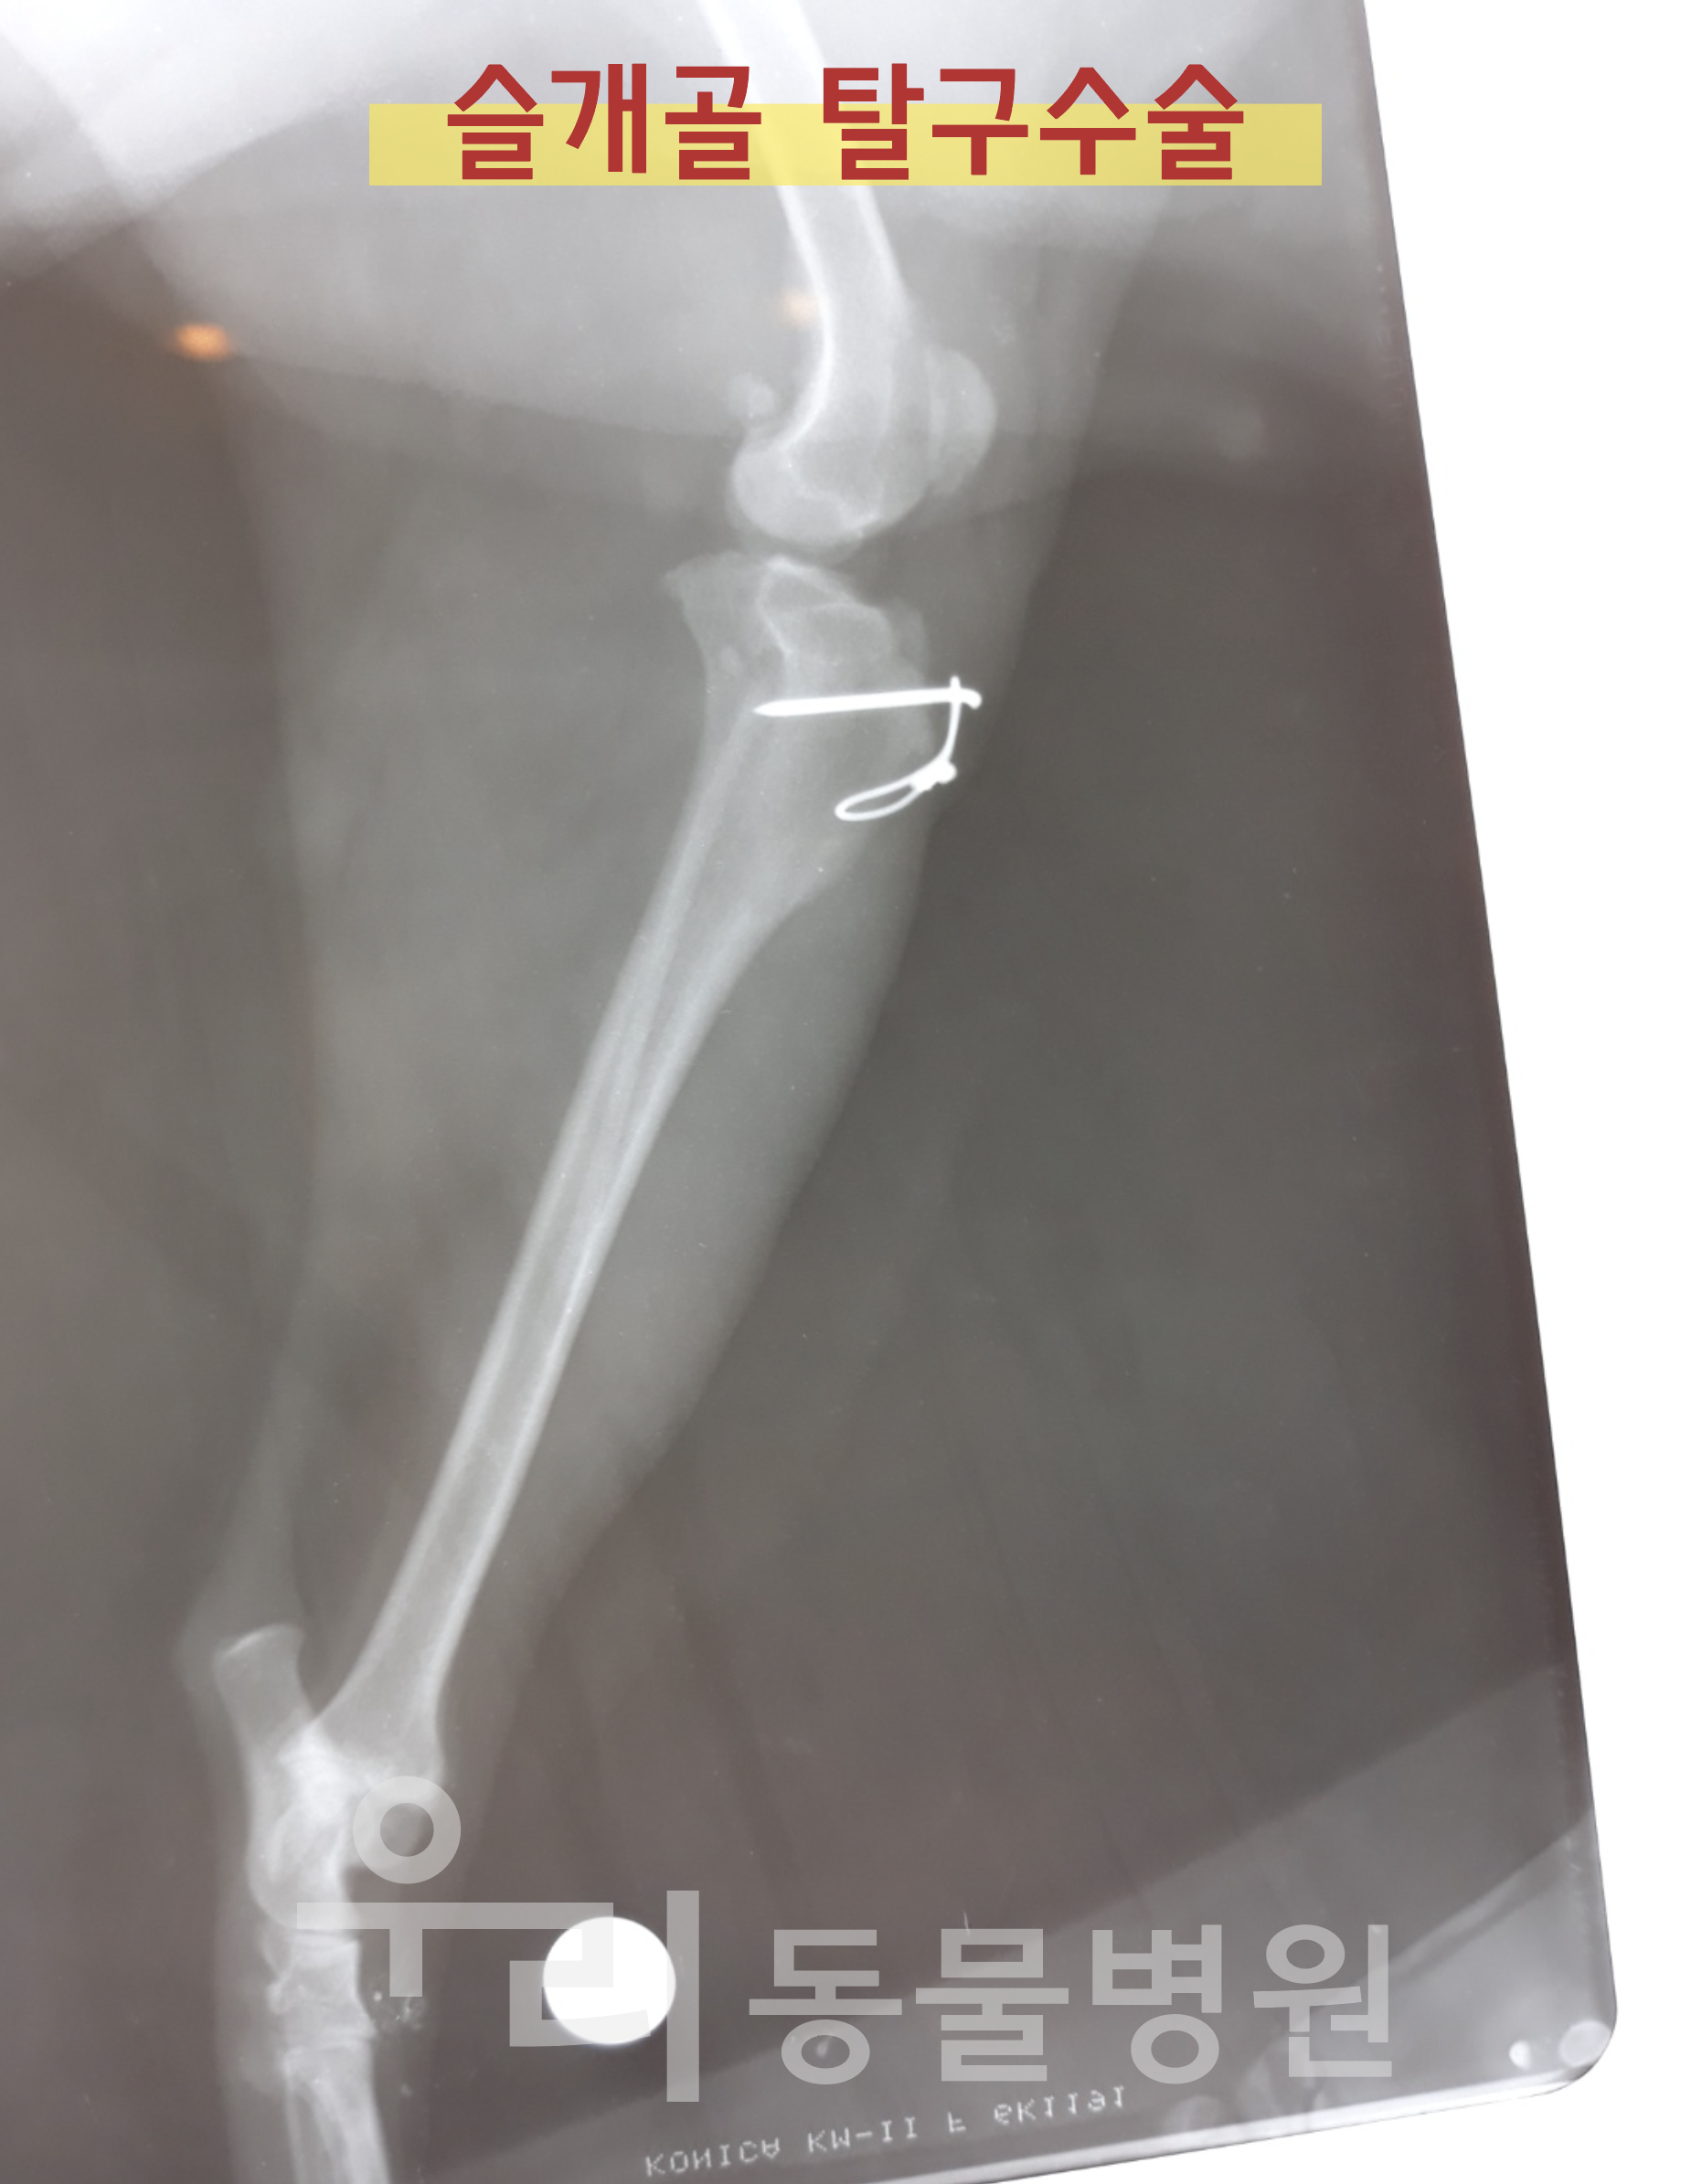

| 연경동물병원 | 대구 북구 연경동 | 수술전문(중성화, 슬개골탈구) | 평일 09:00~19:00, 수 09:00~21:00, 토 09:00~15:00 | 문의 |

| 우리동물병원 | 경북 청도군 화양읍 | 수술전문(중성화, 슬개골탈구) | 전화문의 | 문의 |

대구 북구 연경동에 위치한 연경동물병원은 수술전문 동물병원으로 잘 알려져 있어요. 특히 중성화수술은 물론 슬개골탈구 수술 등 다양한 수술 경험을 가진 곳이라 안심하고 맡길 수 있답니다.

우리동물병원은 청도군청 맞은편에 위치한 반려동물 전문 병원이에요. 초음파, 엑스레이, 혈액검사 등 다양한 장비를 갖추고 있으며, 중성화 수술은 물론이고 항문낭, 슬개골탈구 등 다양한 수술을 전문적으로 하는 곳입니다.

반려동물에게 필요한 모든 진료와 수술이 가능한 곳이라 여러모로 믿음직스러워요. 중성화 수술뿐만 아니라 우리 아이가 아플 때 한곳에서 진료를 계속 받을 수 있다는 것도 큰 장점이죠.